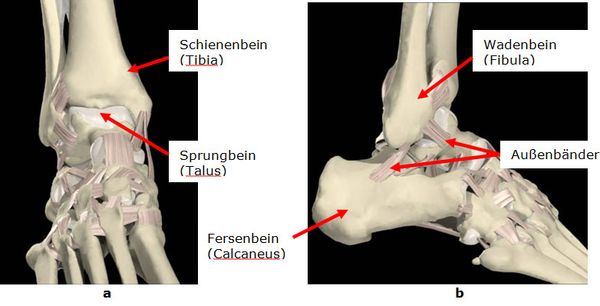

Das obere Sprunggelenk ist ein Scharniergelenk. Die beiden Unterschenkelknochen (Wadenbein, Schienenbein) bilden eine Gabel in der sich das Sprungbein als Rolle bewegt. Zur Sicherung der freien Beweglichkeit ist die Gelenkkapsel vorne und hinten weit und dünn. Die Stabilisierung erfolgt über den Innen-, und Außenbandkomplex sowie mehrere große Sehnen. Das Deltaband zieht vom Schienenbein zu mehreren Fußknochen. Der äußere Bandapparat besteht aus drei Bändern die von der Wadenbeinspitze bis zum Sprung- und Fersenbein ziehen.

Abb.1: a Oberes Sprunggelenk von vorne. b und von der Außenseite.